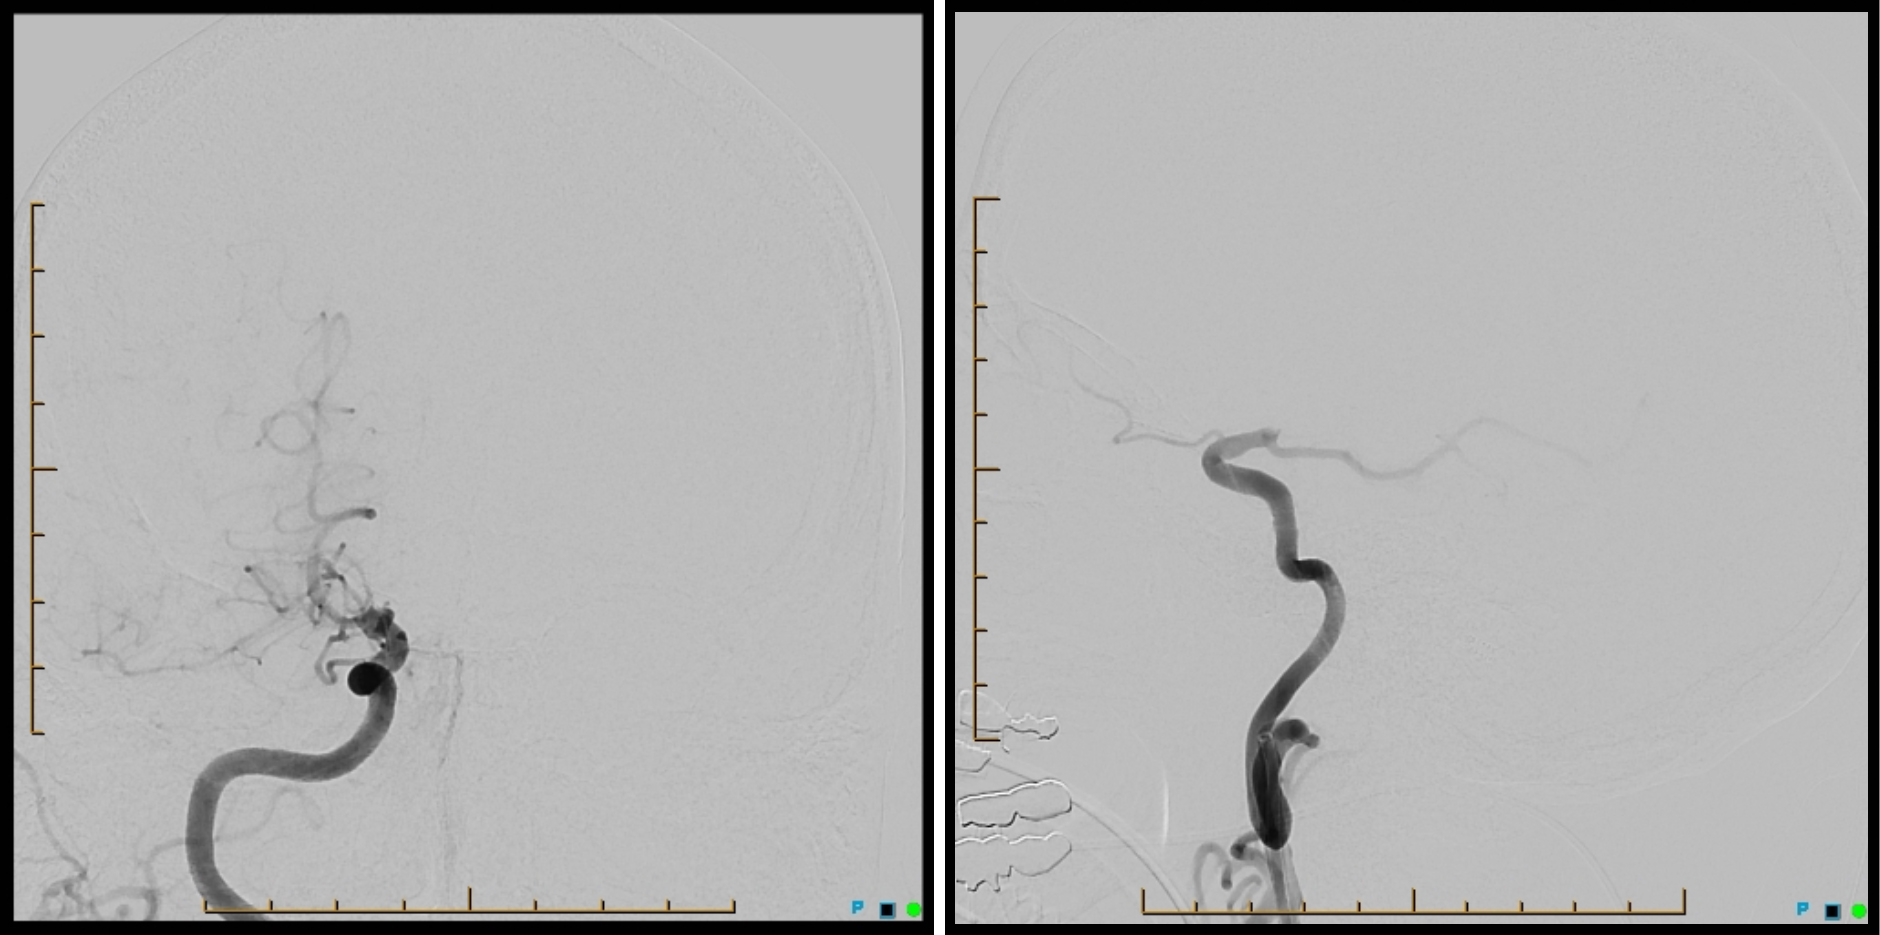

A 68-year-old man had a witnessed fall while riding his bike and was transferred to a local hospital with left hemiparesis. Computed tomography (CT) and CT angiography showed right internal carotid artery type T occlusion (Figure 1). The head CT ASPECTS score was 10.

The patient was sent DTA and a Sine Spin head CT was done (Figure 3). Thrombolysis in cerebral infarction (TICI) 3 was achieved after 1 pass (Figure 4). Time from door to recanalization was 43 minutes. Figure 5 shows the patient’s MRI after 24 hours.